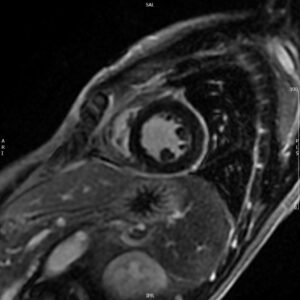

A 52-year old man with a history of diffuse large B cell lymphoma in remission presented with 3 weeks of shortness of breath, cough, fever, and shock. Electrocardiogram revealed sinus tachycardia, diffuse ST segment elevations, PR segment depression, prolonged QTc, and electrical alternans. Bedside echocardiogram was performed, revealing a large circumferential pericardial effusion with tamponade physiology. The patient underwent echo-guided pericardiocentesis with drainage of 400 ml of purulent fluid. Pericardial and blood cultures were positive for Haemophilus influenzae. A CT of the chest was indicative of empyema. Given the patient’s history of rituximab use, autologous stem cell transplant, and profound infection, immunoglobulin levels were drawn and found to be undetectable. The patient received 6 weeks of intravenous antibiotics with IVIG infusions. He was treated with colchicine and aspirin for purulent pericarditis. Two months later, a cardiac MRI was performed, which revealed resolution of the pericardial effusion. No evidence of constrictive pericarditis was noted on MRI, but continued pericardial enhancement was observed. Colchicine was continued for an additional 3 months. The patient made a full recovery at 6 month follow up.